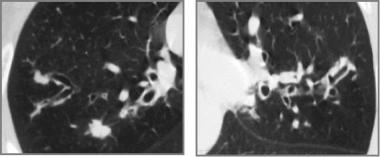

➢空气潴留征:在呼气阶段获得的HRCT很容易发现空气潴留征,约81%的患者可发现过度充气。

图6 左上叶的局部过度充气,且可见支气管壁增厚

➢马赛克症是HRCT扫描中小气道异常的第二个征象,约64%的患者可见马赛克症。

➢支气管壁增厚,约48%-76%的患者可见支气管壁增厚。

图7 支气管壁增厚

➢支气管扩张:支气管扩张是最常见的CT异常,约80%的患者可见支气管扩张,可见柱状型、曲张型和囊状型扩张。

图8 显示支气管壁增厚及“轨道征”,主要在上叶

图9 可见“葡萄串征”

图10 可见支气管周围的磨玻璃样浑浊及过度充气